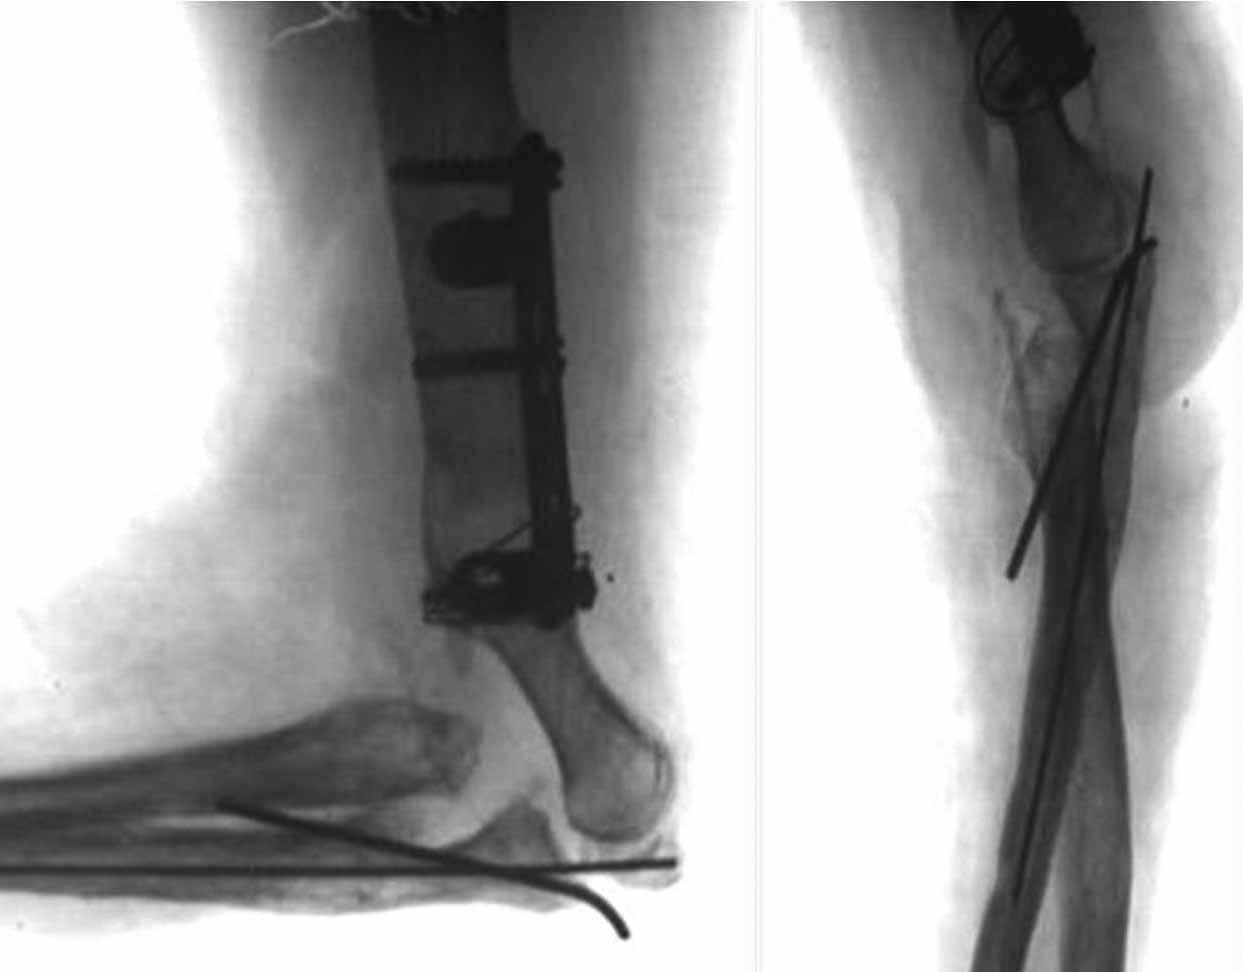

Снимки в проекции "как получилось". Попозже сам уложу на столе правильно.

P1010212.JPG

Данила Курышев 25 Октябрь 2011, 03:03

|

как то так

Оперировали в четверг. Начали с лучевой кости. Легко фиксировали её TEN закрыто ретроградно. Приняли решение ревизовать сустав задним доступом. Открытии локтевую кость , выполнен остеосинтез ульнарным блокируемым гвоздём. Продолжили разрез на плечо. Отломки мыщелков смещены во всех мыслимых направлениях, ротированы, практически лишены связи с мягкими тканями и окружены хрящевой мозолью. Имеются фиброзные сращения отломков плеча с проксимальными отделами костей предплечья. Проксимальный фрагмент плеча упирается в суставные поверхности предплечья. Осумкованные остатки одежды. Операционная картина смещения отломков не позволяла сделать «приблизительную репозицию» - для минимального сближения отломков их было необходимо полностью мобилизовать. Мыщелковые отломки собраны в единый блок, фиксированы спицами и финтами. Сухожилие трицепса сохранило связь с локтевым отростком по наружной поверхности. Локтевой нерв из заднего доступа выявить не удалось. Внутренний надмыщелок - где то сильно спереди. Топографически по краю локтевой кости удалось обнаружить атрофичный тяж, напоминающий раздавленный нерв. С ревизией не упорствовали – повреждение нерва должно быть очень протяжённым и слишком выражен рубцовый процесс с этой зоне. В дальнейшем надо, видимо, будет делать «вставку». После собирания мыщелков состыковали полученный конгломерат с проксимальной частью плеча. Фиксация реконструктивной LCP за наружный, самый крупный фрагмент в районе головки мыщелка. В дефект метафиза – гранулированный ‘’CronOS’’ + ванкомицин. После тщательных санаций и лаважей перешли к закрыванию раны, намереваясь смонтировать Илизарова. Немедленно выяснилось, что как раз на самой середине раны, над локтевым отростком края кожи сводятся с критическим натяжением. Кости предплечья при малейшем движении в суставе вывихивались кнаружи, что потребовало фиксации спицей сустава (луч-головка). Разгибание в суставе также не давало возможности ушить кожу без натяжения. Причиной помехи виделось изменение взаимоотношений тканей и рубцовый конгломерат по передней поверхности плеча и локтевого сустава, после репозиции отломков сместившийся кпереди. Операционный отёк был минимален. Сразу родилось запоздалое соображение. Было бы не лишним перед открытым вмешательством наложить дистракционный аппарат, дать дозированное удлинение за предплечье и создать запас пространства, выполняя некоторый «таксис» отломков плеча, а не идти сразу на прямую репозицию. Почему то задним умом думается, что это значительно бы облегчило работу с мягкими тканями. Рана была закрыта с натяжением краёв при помощи эластичных нитей на степлерных скобках. В таких условиях пришлось отказаться от монтажа илизаровского АВФ и активизации сустава – теперь рану надо закрывать этапно. Смонтирован ExFIX c шарниром по осевой спице – сама спица удалена. Наложен VAC на рану. Оставили катетер в сплетении, обезболивали 3 суток маркаином.

Ну и ещё, а после операции можно сделать рентген так, чтобы самим было понятно, где кости, а где металл? Как минимум, некорректно!